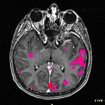

Malformaciones Arteriovenosas Cerebrales

Esta entidad es una patología compleja y heterogénea en donde existe una comunicación anormal entre las arterias y venas del cerebro, son congénitas aunque algunos autores han reportado de forma aislada algunas malformaciones arteriovenosas (MAV´s) que se forman después del nacimiento.

Embolización de Malformaciones

Arteriovenosas Cerebrales

El tratamiento de las malformaciones cerebrales depende de múltiples factores: Tamaño de la MAV, Localización, Tipos de arterias que alimentan a la MAV, Drenaje venoso de la lesión, Otros datos de la Angioarquitectura, Síntomas. El procedimiento se realiza con el paciente despierto, utilizando anestesia local y con un abordaje inguinal convencional.